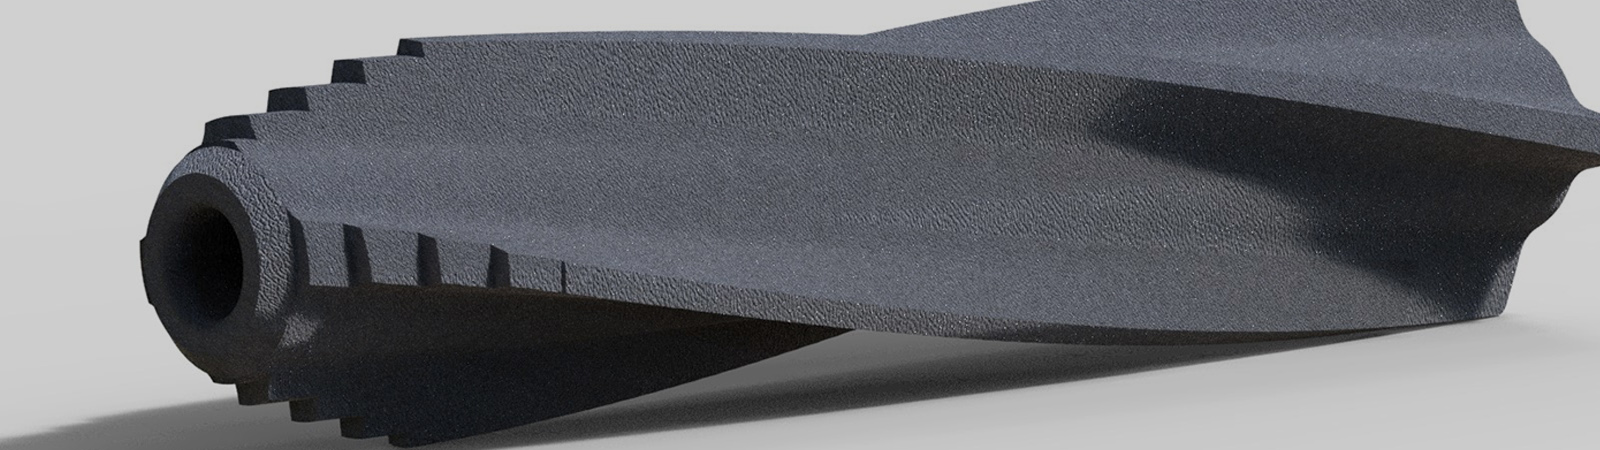

zurückTORPEDOISG-Fusions System

Torpedo bietet eine minimalinvasive Option für die Behandlung von ISG-Dysfunktionen. Das wendelförmige CST-Profil® mit seinem conical-spiral-turn begünstigt einen idealen Pressfit-Kontakt zwischen Implantat und Knochen und erhöht die Fusionskraft in Zugrichtung um ein Vielfaches. Die wendelförmige Profilgeometrie stabilisiert die Bewegungen im ISG Gelenk auch in der Ebene senkrecht zu den Gelenkflächen. Spezielle Oberflächenbehandlungen erzeugen eine definierte und hydrophile Implantatoberfläche.

zurückTORPEDOAugmentation

Torpedo erlaubt bei Frakturen des Saktrums durch seine Fenesteriung im conical-spiral-turn eine feste Verankerung des Implantates mittels Zementinjektion. Der Zement wird durch eine steuerbare Applikationshülse durch die Kanülierung des Implantates eingebracht. Dabei kann jede Austrittsöffnung gezielt angesteuert werden und somit dezidiert in die entsprechenden Voids injiziert werden.